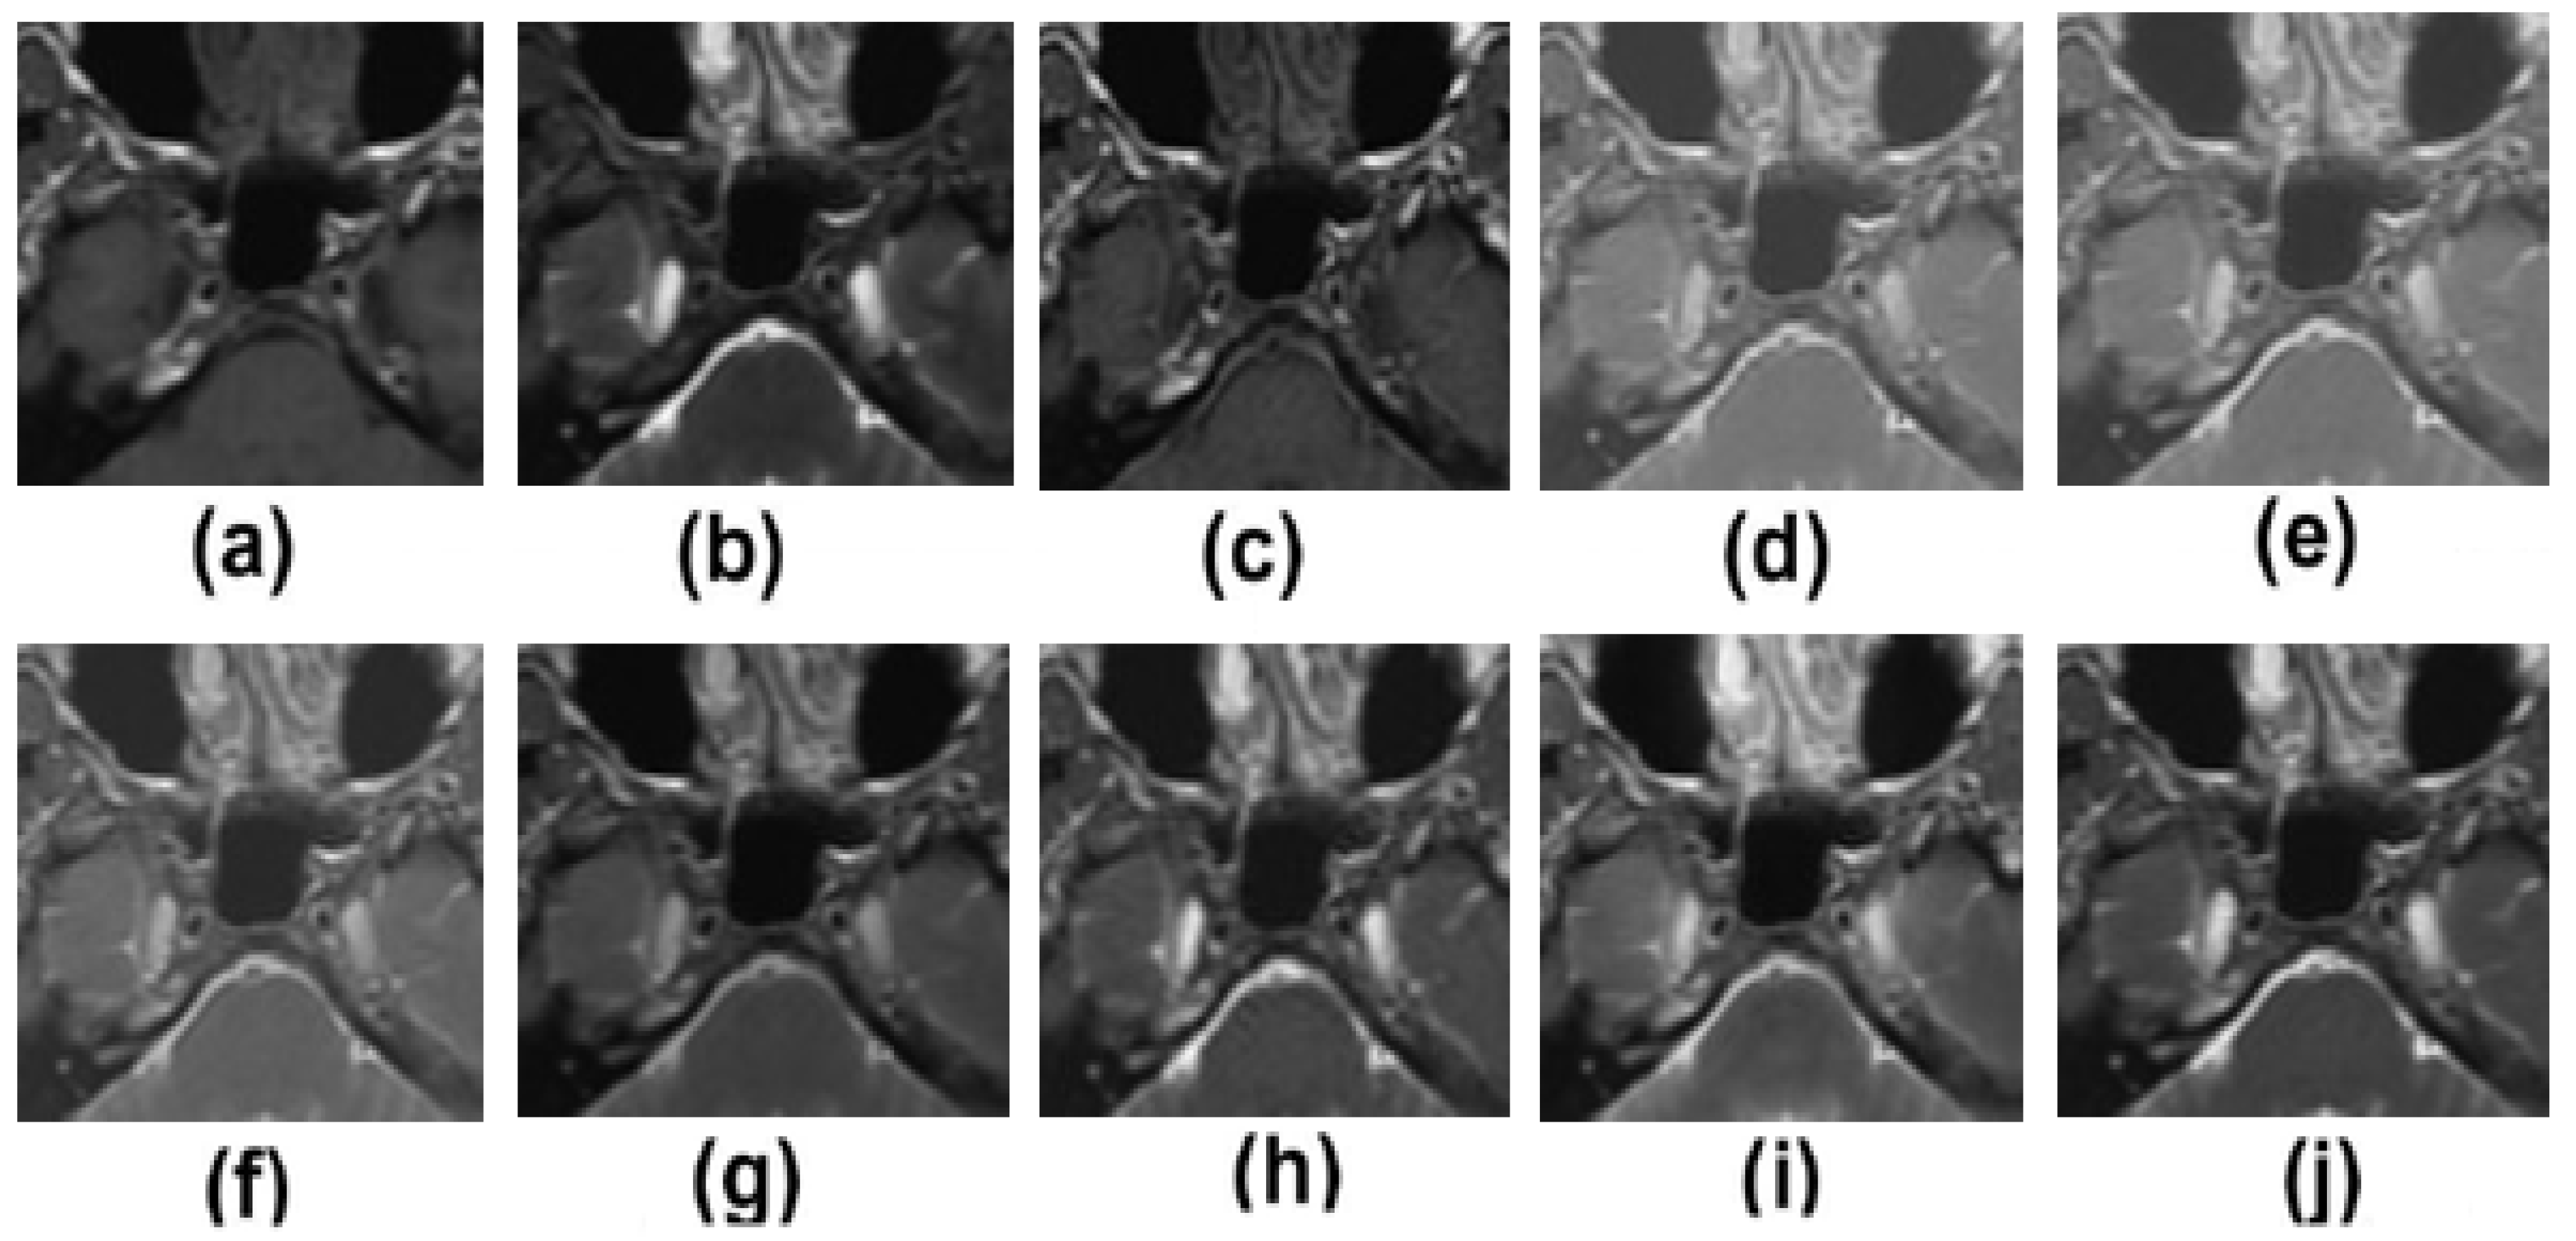

5.2. Results and Discussion